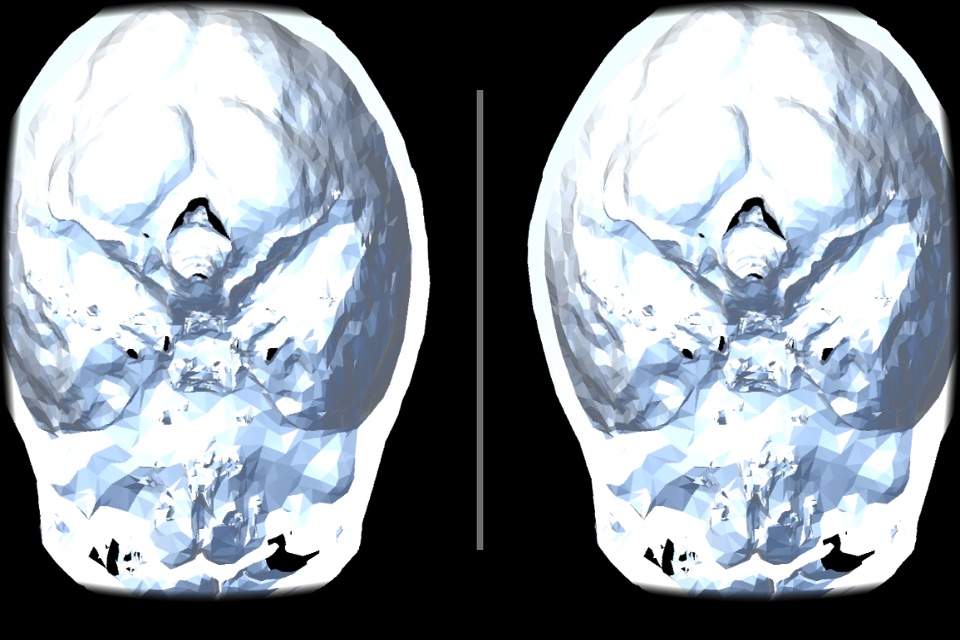

VR Body Guideは、まるで目の前にあるように、

人体の内部の様子をリアルに眺めて、

人体の不思議を楽しむことができる、医学教育用アプリです。

実際のCT画像から起こされた、本物の内臓のモデルを、間近に見ることができます

(これは似せて作られたモデルではありません!)。

・鑑賞するモデルは「頭部」と「胴体」の2種類です。

頭部は脳、頭蓋骨、皮膚のそれぞれの表示をON/OFFできるようになっています。